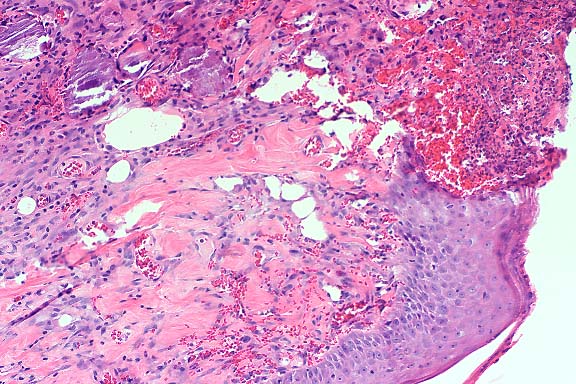

Contributor's Diagnosis and Comments: Lung: Pneumonia, granulomatous, multifocal, moderate, with vacuoles (lipid).

Both CFA and IFA have been administered intravenously to enhance

antibody production and to study the effects of injury and repair

to the lung. Multiple focal granulomas are formed subpleurally

where adjuvant emboli are often sequestered due to vascular distribution

in the lung. Type II alveolar epithelial cells become hyperplastic,

and the alveolar septa become thickened. Similar lesions may occur

with intramuscular (IM) and subcutaneous (SC) injection of CFA

and IFA. Granulomas resulting from embolism after SC and IM inoculations

may occur in glomeruli, liver, heart, and other organs. These

emboli probably result from the entrance of adjuvant into blood

vessels from necrotic tissue near the inoculation site. Lipid

containing macrophages mobilized from these sites may also become

sequestered in the lung and cause foci of granulomatous inflammation.

These pulmonary granulomas usually resolve and are not detected.